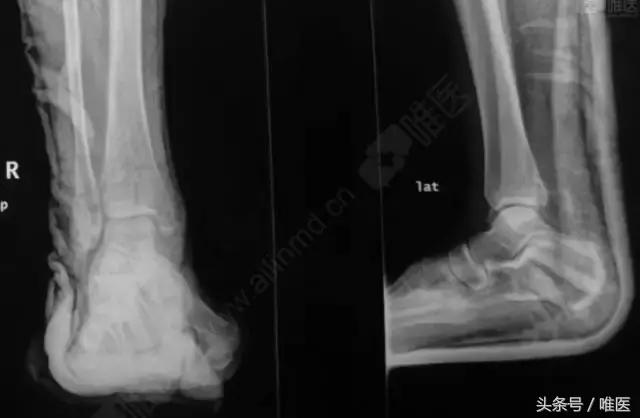

CT二维重建: 右侧踝关节骨折

L-H分型:旋后外旋型 IV度;

Danis-Webber分型:B型

治疗前影像